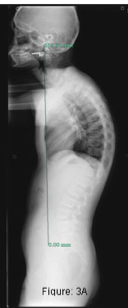

Cobb angle

(measures whole curvature of spine in order to determine overall impact of anterior wedging)

What is the Cobb Angle?

Used to determine the maximum angle of curvature= overall impact of antior wedging

–> guides tx of Scheuermann’s Kyphosis

3. Kyphosis >75deg